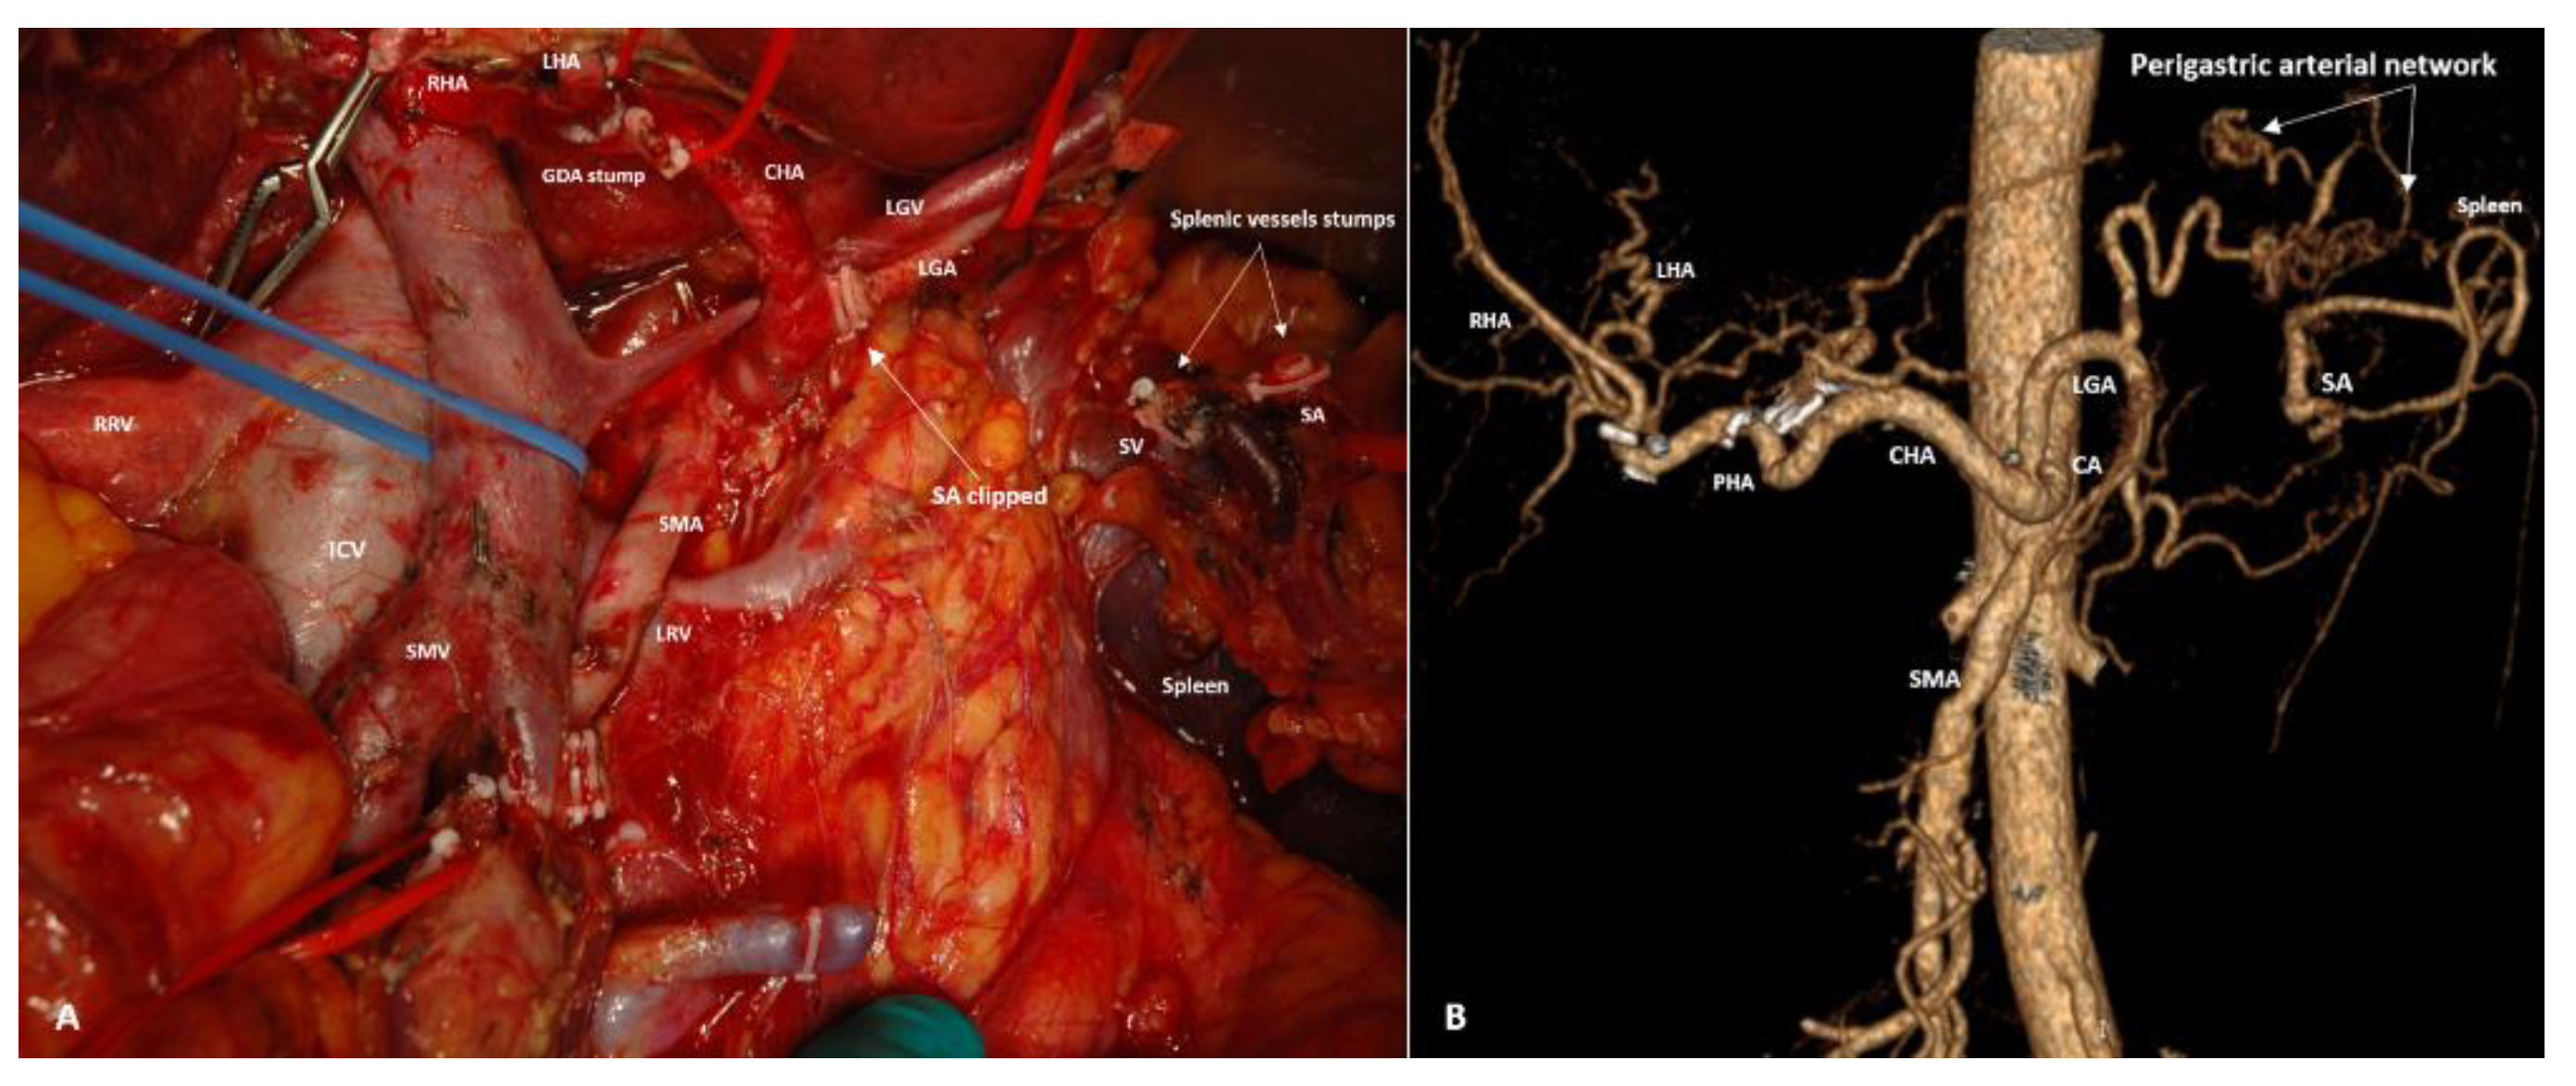

3.3. Spleen-Preserving Pancreatectomies with Resection of the Splenic Vessels, Other than Distal Resections

3.4. Spleen-Preserving Pancreatectomies with Resection of the Splenic Artery (Vessels) for Border Line Resectable and Locally Advanced Pancreatic Head Cancers